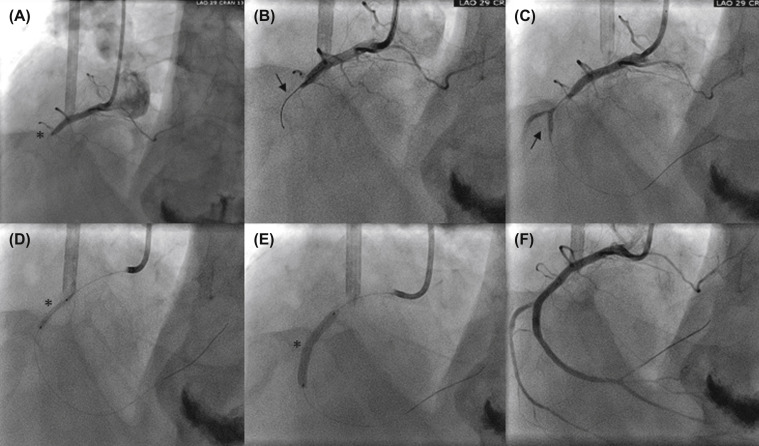

Coronary artery ectasia (CAE) is an uncommon cardiovascular disorder characterized by diffuse dilatation of the coronary arteries, which can be